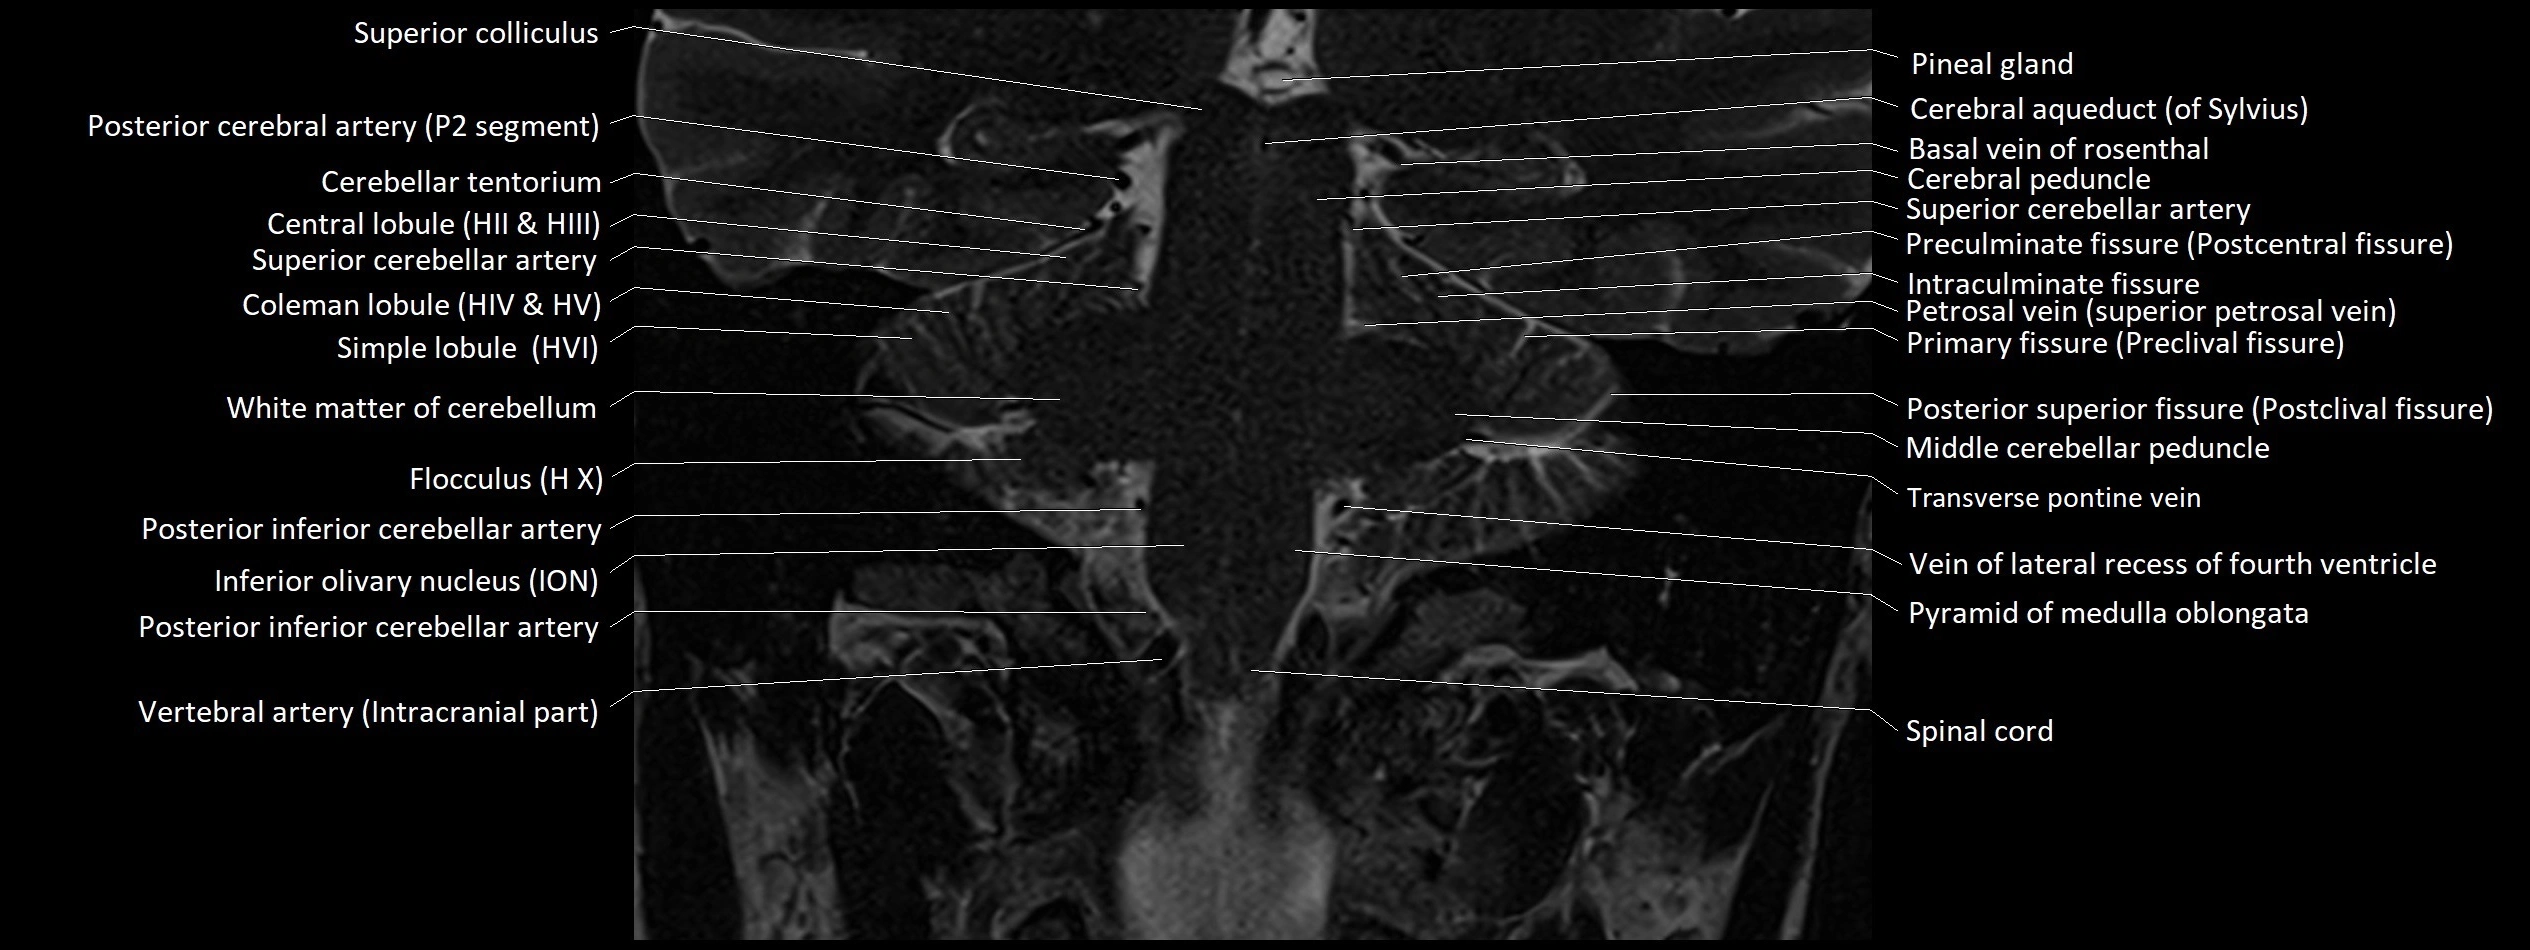

- Cerebellar tentorium

- Central lobule

- Central lobule (II & III) of Cerebellum

- Anterior quadrangular lobule

- Anterior quadrangular lobule (HV) of cerebellum

- Anterior quadrangular lobule (HlV) of cerebellum

- Simple lobule

- Simple lobule (HVI) of cerebellum

- Flocculus

- Posterior inferior cerebellar artery

- Inferior vestibular nucleus

- Lateral vestibular nucleus

- Medial vestibular nucleus

- Superior vestibular nucleus

- Middle cerebellar peduncle

- Posterior cerebral artery (P2 Segment)

- Transverse pontine vein

- Vein of lateral recess of fourth ventricle

- Pyramid of vermis (VIII)